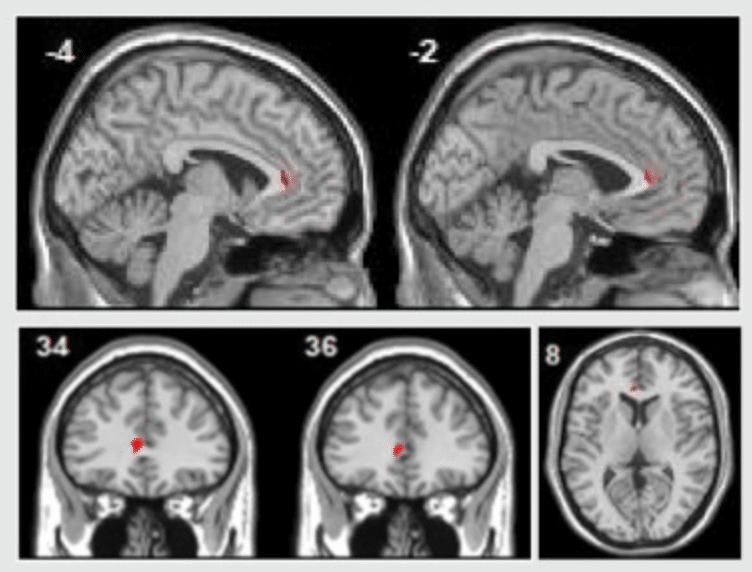

Majör depresyon hastaları psikolojik terapinin ardından sol rostral ön singulat kortekslerinde aktivite artışı göstermişlerdir. Görsel: Sankar et al, 2018

Bir başka bulgu bilişsel davranış terapisi ve psikodinamik terapi sonrasında hastaların sol rostral ön singulat alanlarındaki aktivite artışını gösteriyor (yukarıdaki görsele bakınız; sağlıklı kontrol gruplarının bu değişimi göstermemesi bulgunun sadece görüntü izleme görevlerindeki geçen zaman ya da pratik yapma etkisine bağlı olmadığını belirtiyor). Bu beyin bölgesi, amigdala aktivitesini baskılamak gibi etkilerle, çekirdek duygu işlemlerini gerçekleştiren bölgelerle güçlü şekilde bağlantılıdır. Daha önceki kanıtlar ön singulat ve amigdala arasındaki bağlantıların majör depresyonda daha zayıf olduğunu gösteriyor. Bu durum majör depresyon hastalarında duyguların neden daha yoğun bir şekilde hissedildiğini açıklıyor. Yani öyle gözüküyor ki psikoterapinin etkilerinden biri de bu zarar görmüş bağlantının yeniden inşası olabilir. Meta-analiz bize bu inşanın nasıl gerçekleştiğini kesin olarak gösteremese de ihtimallerden biri “bilişsel yeniden değerlendirme” gibi yöntemlerle zorlu deneyimleri yorumlamanın yeni yollarını bulmak olabilir.